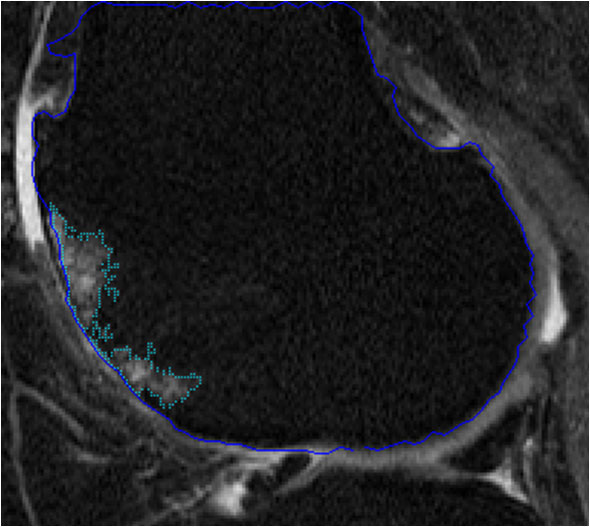

The majority of the work during the past five years has been supported by a successful NIH grant. (R01AR056664). The goal of this study was to develop and validate several software-based measures of knee OA from MRI data sets. Much of the group’s recent effort has been directed at accomplishing the aims of this grant proposal. We now have fast quantitative methods in place for cartilage morphometry (1-2), bone marrow lesion (BML) (3), and osteophyte volume (4), and have looked at associations of these measures with pain. Methods are in place to assess large numbers (several hundred) subjects for multiple disease-related structures, which will facilitate future higher power studies of knee OA. We are actively seeking additional funding to support the next phase of the program.

Bone marrow lesion volume |